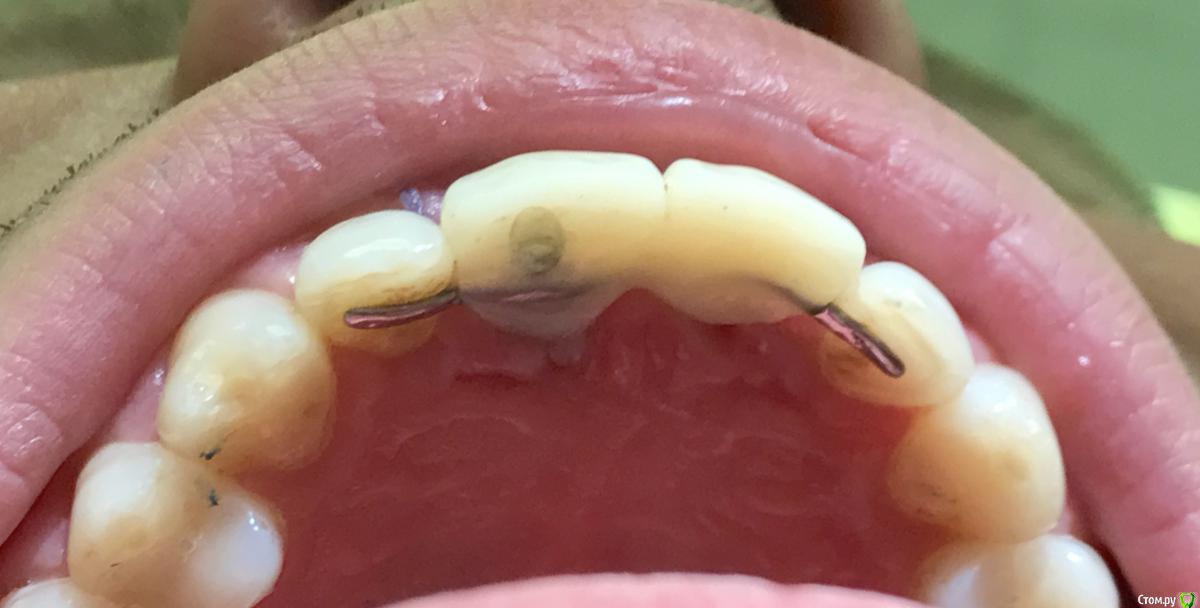

Astronaft Опубликовано 22 июня, 2018 Автор Поделиться Опубликовано 22 июня, 2018 У меня следующие размышления.1. Без времянки никак.2. Если резать - сосочек сразу затупится и укоротится. Я готов туннель сделать от клыка и прибить мембрану пином - лишь бы не резать. Биоосс мне нравится тем что будет держать обьем пару десятков лет, выступая в роли щита. Даже если кость не вырастет, все равно гранулы будут держать десну.Хочу имплант заглубить на 3 мм от медиальной кортикалки. При этом имплант со стороны 12 будет на 2 мм не в кости.http://miworks.weebly.com/uploads/1/6/8/7/16879370/2_5_orig.jpg Ссылка на комментарий

Иван911 Опубликовано 23 июня, 2018 Поделиться Опубликовано 23 июня, 2018 У меня следующие размышления.1. Без времянки никак.2. Если резать - сосочек сразу затупится и укоротится. Я готов туннель сделать от клыка и прибить мембрану пином - лишь бы не резать. Биоосс мне нравится тем что будет держать обьем пару десятков лет, выступая в роли щита. Даже если кость не вырастет, все равно гранулы будут держать десну.Хочу имплант заглубить на 3 мм от медиальной кортикалки. При этом имплант со стороны 12 будет на 2 мм не в кости.http://miworks.weebly.com/uploads/1/6/8/7/16879370/2_5_orig.jpgЯ так думаю, здесь основной проблемой будет стабилизация импланта , если даже вестибулярка останется , не факт что выйдет установить имплант без перфорации резцового канала. был похожий случай , только там еще было два свища вестибулярно, торк около 10 , графт Bio-oss, сст с бугра закрыл свищи, имплант брал Straumann slaactive( думаю, может с этим связано то что торк не потерялся) сейчас бы делал индивидуальный формирователь при низкой силе фиксации. Ссылка на комментарий

Astronaft Опубликовано 24 июня, 2018 Автор Поделиться Опубликовано 24 июня, 2018 Система Астра 13мм запланировал.Пучек надеюсь обойти. Карен, "заткнуть корнем"- на манер idr, а позже извлечь его? Т.е. просто оградить временно от полости рта. Ссылка на комментарий